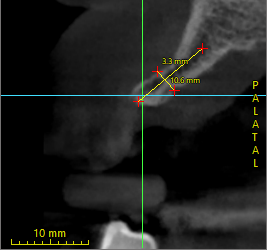

Implant treatment planning for #3,4,11,13,14

Hi everyone, got some questions for y’all experts.

The patient is my father in law, who has given me freedom to do all that I recommend except he really doesnt want to extract 1,2,15,16.

After studying the CBCT, I have some thoughts for these following sites, please help me double check and see if my thought process is correct.

Thank you all…